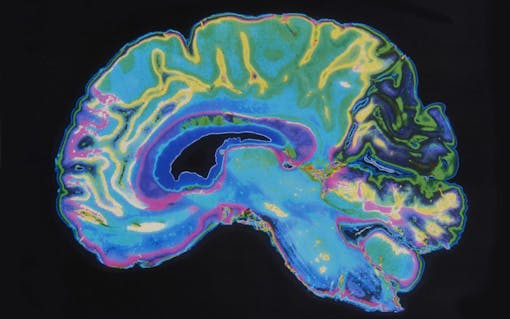

Scientists from Weill Cornell Medicine reviewed recordings from fMRI scans that suggest these substances essentially flatten the landscape of your brain, making it easier to jump between tasks.

In the study, researchers tracked the effects of LSD and psilocybin on brain activity using functional magnetic resonance imaging (fMRI) recordings of the brain activity of volunteers. Each volunteer underwent two scanning sessions. One session included a dose of LSD or psilocybin, the other a placebo.

Data from the recordings revealed that participants could transition between activity states more easily, allowing “for more facile state transitions and more temporally diverse brain activity.” The authors added, “more broadly, we demonstrate that receptor-informed network control theory can model the impact of neuropharmacological manipulation on brain activity dynamics.”